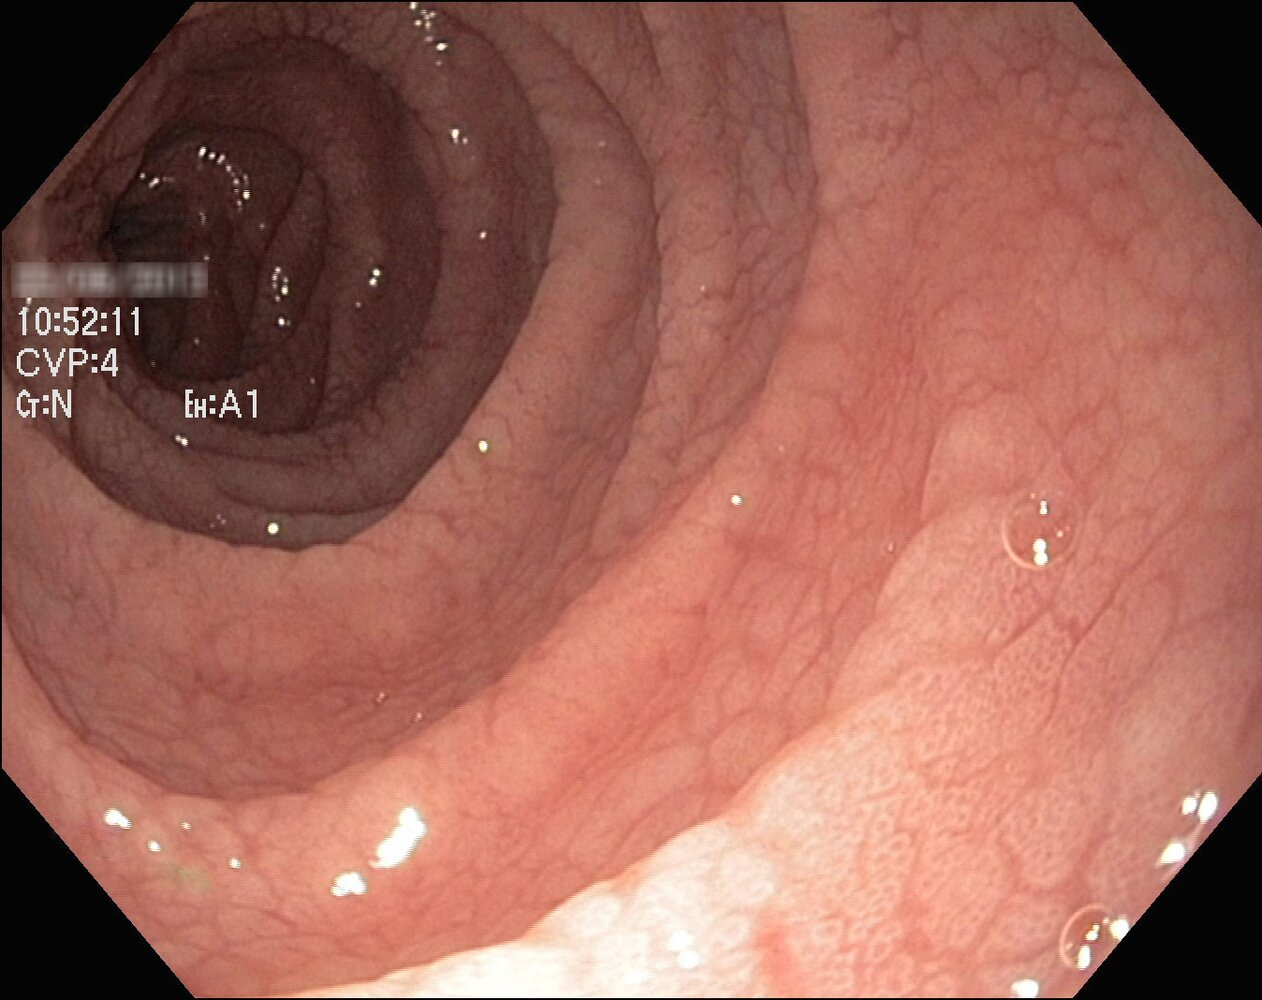

Endoscopy

• EGD with small intestine biopsy (confirmatory test)

• Indications: positive serology or high clinical suspicion despite negative serology

• At least 5 duodenal biopsies should be taken (with ≥1 from duodenal bulb)

• Histological findings (Marsh classification):

• Intraepithelial lymphocytosis

• Crypt hyperplasia ( image 2)

• Villous atrophy ★ ( image 3)